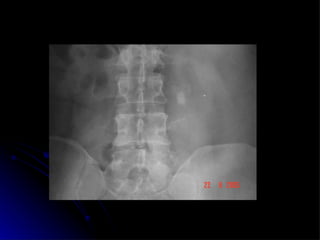

Lingeman JE; Surgical management of urinary lithiasis .  In Campbell´s Urology. 8 ed. 2002 7 cm x 5,5 cm

Lingeman JE; Surgicalmanagement of urinary lithiasis . In Campbell´s Urology. 8 ed. 2002 7 cm x 5,5 cm

• #16 Poderia um cálculo destes ser removido por laparoscopia????? O que voces pensam????? Vamos abordar nestes 10 minutos a definição e classificação dos cálculos coraliformes, as indicações de cirurgia aberta, a técnica cirurgica ,experiencia mundial, resultados e por fim considerações finais.